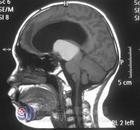

• 小兒顱咽管瘤

628健康網為您分享有關小兒顱咽管瘤的癥狀,小兒顱咽管瘤的治療方法,小兒顱咽管瘤的預防知識,小兒顱咽管瘤的癥狀圖片,小...